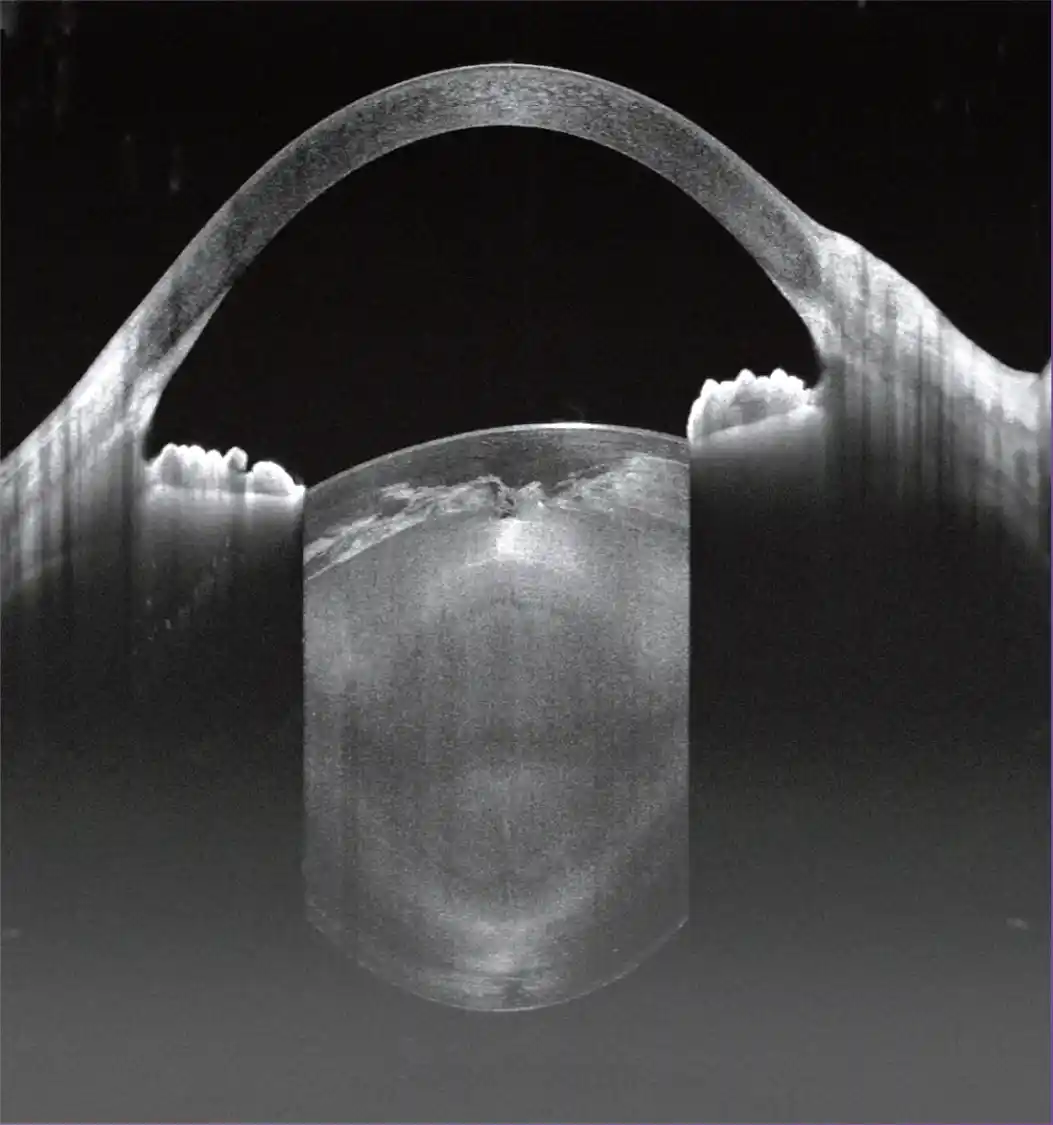

Głęboka penetracja

Urządzenie zapewnia większą głębokość skanu w tylnym odcinku (12 mm) i przednim odcinku (15 mm), co jest szczególnie korzystne w obrazowaniu ciała szklistego, naczyniówki oraz struktur przedniego odcinka

Wizualizacja przeszkód

Długość fali 1060 nm jest szczególnie korzystna do skanowania pacjentów z zaćmą i zmętnieniami ciała szklistego

Analiza Segmentu Przedniego (AS)

Pomiary ilościowe, parametry panoramiczne, mapa grubości rogówki, głębokość komory przedniej i kąt przesączania